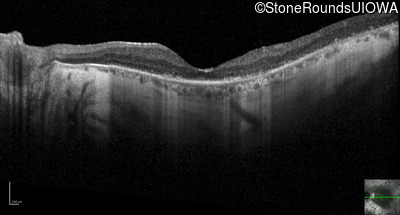

Optical Coherence Tomography - Left - 20/80 +2

Exemplar / OCT Stack